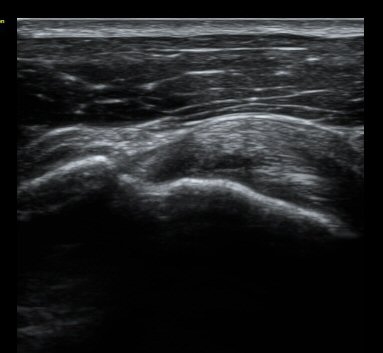

ȸÀü±Ù°³°£°Ý Ⱦ´ã³à°Ë»ç¿¡¼­ ƯÀÌ ¼Ò°ßÀ» º¸ÀÌÁö ¾ÊÀ½(±×¸² 1).

À̵ιڱٰí¶û¿¡¼­ À̵ιڱÙÀÌ Á¤»óÀûÀ¸·Î °üÂûµÇ°í ƯÀÌ ¼Ò°ßÀ» º¸ÀÌÁö ¾ÊÀ½(±×¸² 2).